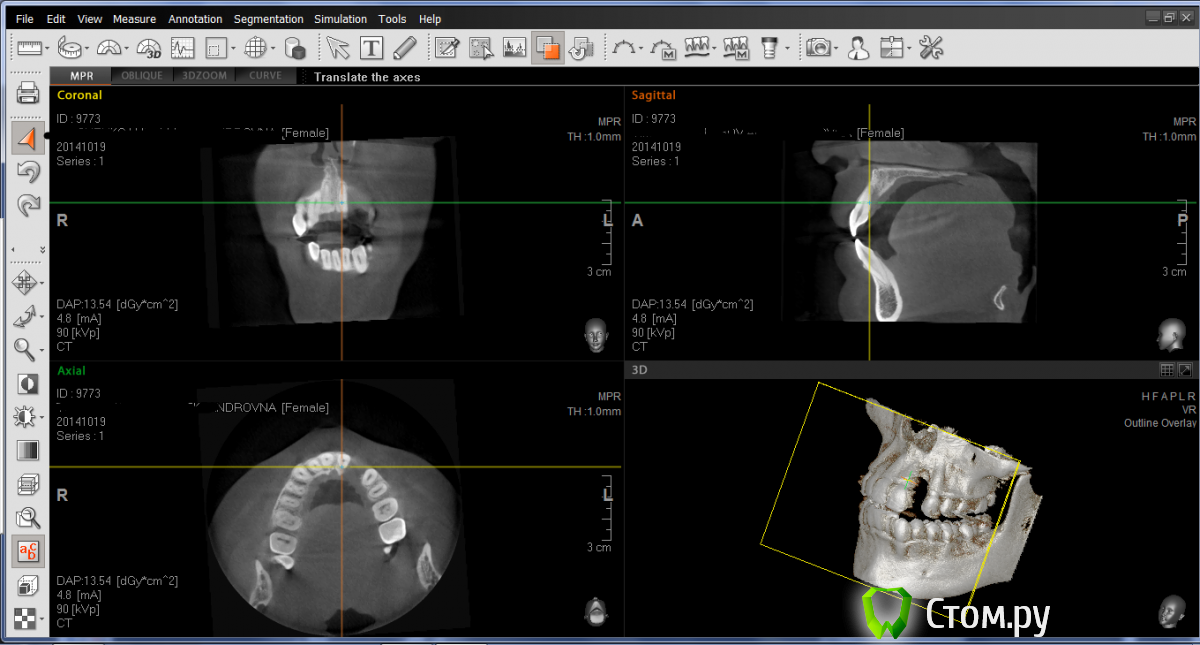

LuBoF Опубликовано 22 октября, 2014 Поделиться Опубликовано 22 октября, 2014 Добрый всем день. Мне нужна Ваша помощь и консультация в следующем вопросе: у меня удален 2 зуб сверху. Стоматолог говорит нужно наращивать костную ткань для имплантации, еще говорит что нужно удалить соседний 1 ый зуб, тк с одной стороны у него нет кости тоже, и поэтому костный блок не приживется. Удалять нормальный зуб я не хочу. Посоветуйте что делать и как быть в этой ситуации!! Ниже приклепляю свою КТ. Может конечно не тот ракурс, если надо под другим углом, тогда я переделаю. Ссылка на комментарий

LuBoF Опубликовано 22 октября, 2014 Автор Поделиться Опубликовано 22 октября, 2014 Вроде выставила. Если что не судите строго. Ссылка на комментарий